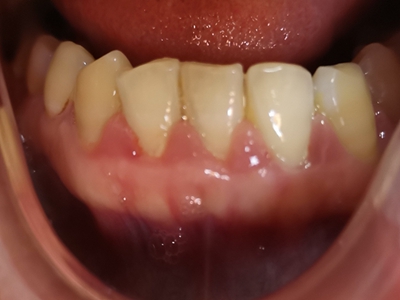

牙龈炎是发生于牙龈组织的炎症,患者可出现牙龈出血伴肿胀、发红、正常形态改变和偶尔不适等症状。本病主要由口腔卫生状况差导致,包括口腔不洁、牙菌斑等,诊断依据临床检查,治疗包括专业牙齿清洁和加强家庭口腔卫生。

牙龈炎可先引起牙齿与牙龈之间的沟(龈沟)加深,然后牙龈充血,炎症围绕一个或多个牙齿,伴牙龈乳头肿胀和易出血。一般无痛,可自行消退,也可维持轻度炎症数年。

牙龈炎患者可通过改善口腔卫生控制疾病,同时使用抗菌漱口液,如复方氯己定含漱液,并进行彻底的洁治处理。必要时,重新修整修复体的不良外形,并祛除局部刺激因素。